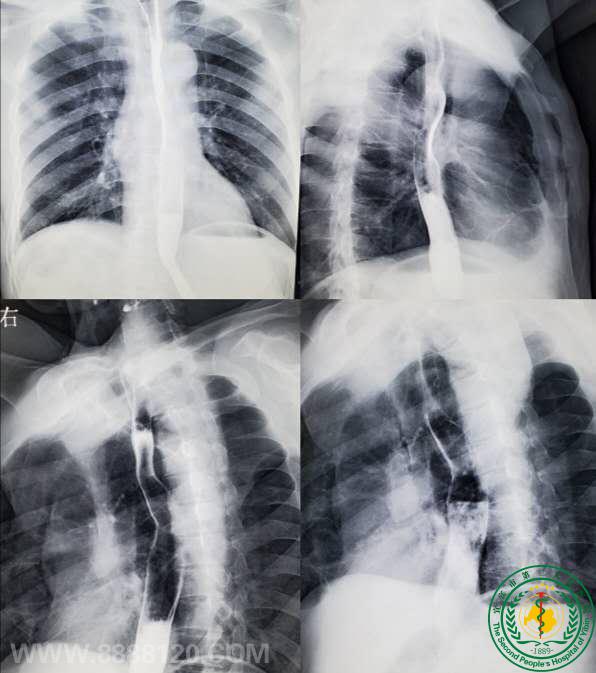

宜宾市第二人民医院 图文